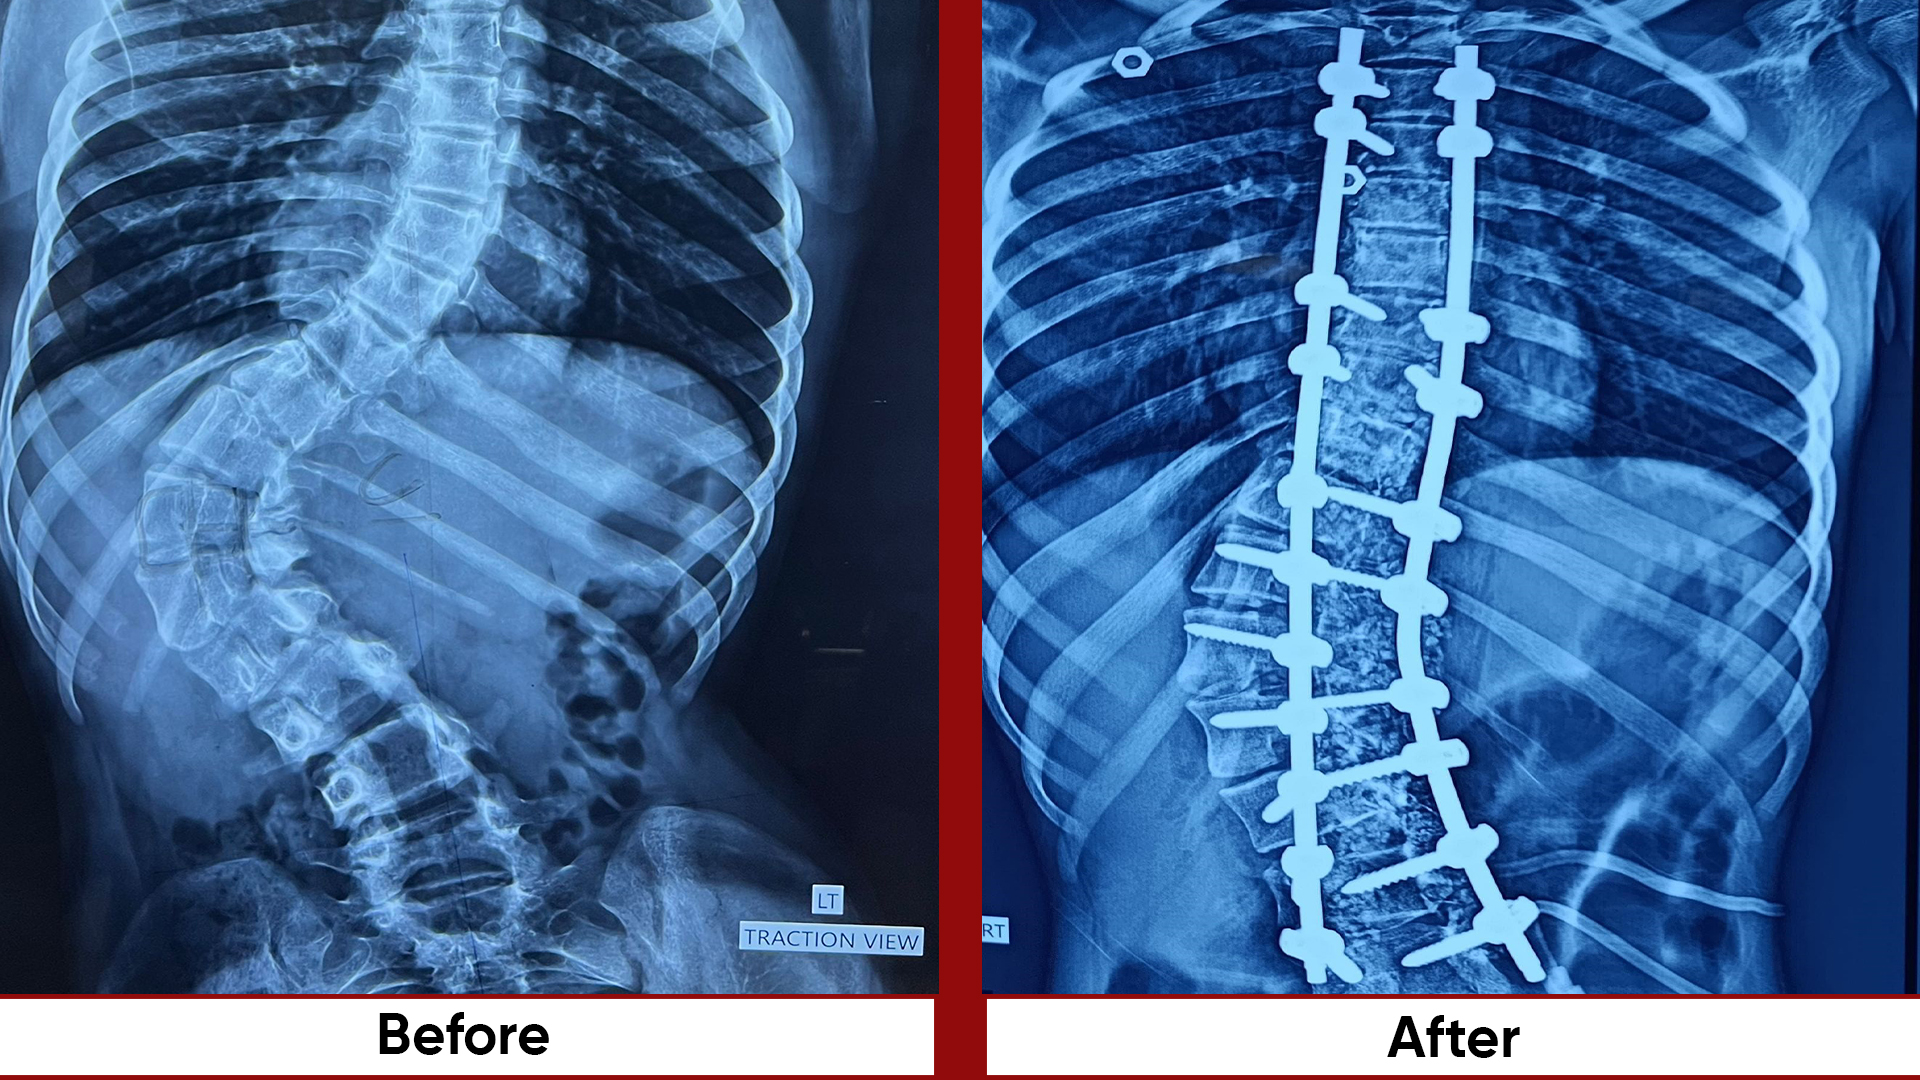

• Fracture Management (simple and complex trauma)

• Deformity Correction (limb lengthening, bowlegs, knock knees)

• Osteotomies (bone realignment surgeries)